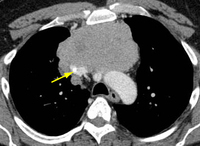

Tomografia computadorizada (TC) do tórax mostrando timoma em estádio IVA de Masaoka-Koga com derrame pleural (seta vermelha) e vastas metástases pleurais (seta amarela) juntamente à parede torácica posterior

Do acervo de Cameron Wright, MD; usado com permissão